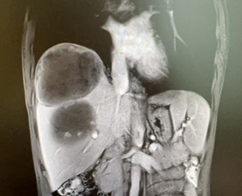

新辅助(两次HAIC和两个周期靶免治疗)后CT

由于病人一般情况较好,肝功能良好(Child-pugh A级),经多学科会诊临床确认肿瘤为IIb期肝细胞癌,属于可切除性肝癌,但存在高危复发因素,建议先行新辅助治疗后手术切除。经两次肝动脉关注化疗(HAIC)(奥沙利铂+5-Fu+亚叶酸钙方案)和两个周期的靶向免疫治疗(仑伐替尼+帕博利珠单抗方案),第二次介入造影是肿瘤血供不明显,第二次介入治疗4周后复查CT提示肿瘤缩小不明显但坏死征象明显,经MRI证实仍有少许血供,于是经多学科会诊后决定行前入路右半肝切除术。